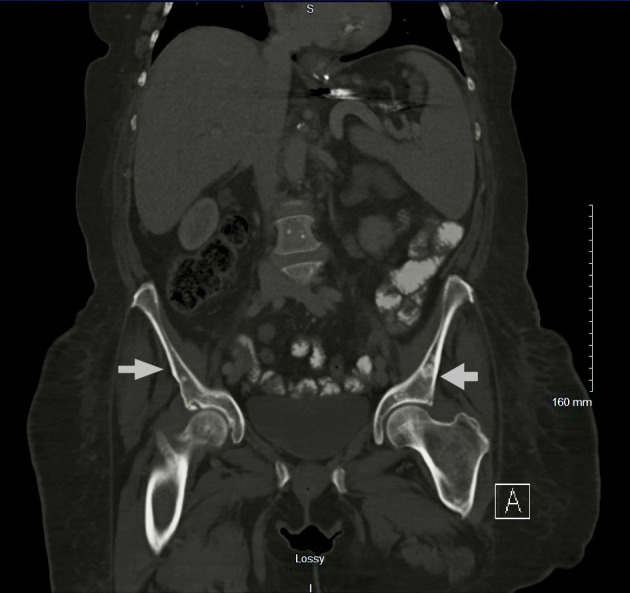

肥大细胞白血病(MCL)是一种罕见的侵袭性系统性肥大细胞增多症(SM),通常累及骨骼。这通常表现为骨质疏松伴局灶性溶骨病变和病理性骨折。成骨细胞(硬化)病变在MCL中很少见。椎体是最常见的骨受累部位,轴骨以外的病变极为罕见。以成骨细胞病变为表现的MCL在文献中已有报道,然而,在阑尾骨骼中没有成骨细胞病变的报道。在此,我们报告一例罕见的急性白血病MCL,表现为弥漫性成骨细胞/硬化性骨病变,累及肋骨、胸椎、腰椎和骨盆,无病理性骨折。

Mast cell leukemia (MCL) is a rare and aggressive form of systemic mastocytosis (SM) that commonly involves the bone. This often presents as osteoporosis with focal osteolytic lesions and pathological fractures. Osteoblastic (sclerotic) lesions are rarely seen in MCL. The vertebral bodies are the most common site of bone involvement, with lesions outside of the axial skeleton being extremely rare. MCL presenting with osteoblastic lesions has been reported in the literature, however, there are no reported cases of osteoblastic lesions in the appendicular skeleton. Here we report a rare case of acute aleukemic MCL that presented with diffuse osteoblastic/sclerotic osseous lesions involving ribs, thoracic spine, lumbar spine and pelvis without pathological fractures.